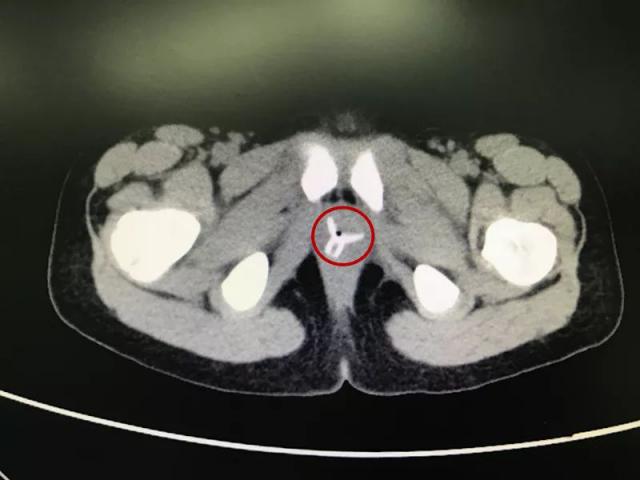

2018 年,安徽亳州 7 岁女孩楚楚(化名),从前一年暑假开始,奶奶发现楚楚的内裤上面有淡黄色粘液,似乎是阴道分泌物,会阴部还有些红肿,便立刻将这事儿告诉了孩子妈。当地医院怀疑是"阴道炎",但几经治疗情况也没有好转,分泌物还是很多,有时甚至一天要换两、三条内裤。一年后再次就诊,CT 结果出来后发现楚楚的阴道内有一个" Y "形的异物,这应该就是"会阴红肿,分泌物增多"的罪魁祸首。

随后在家长的再三询问下,楚楚想起去年暑假,自己和小伙伴玩"医生病人过家家"游戏时,小伙伴曾将一个小吸盘从她的下体塞入,但她事后并没有告诉家人。也就是说,异物已经在楚楚体内待了将近一年。